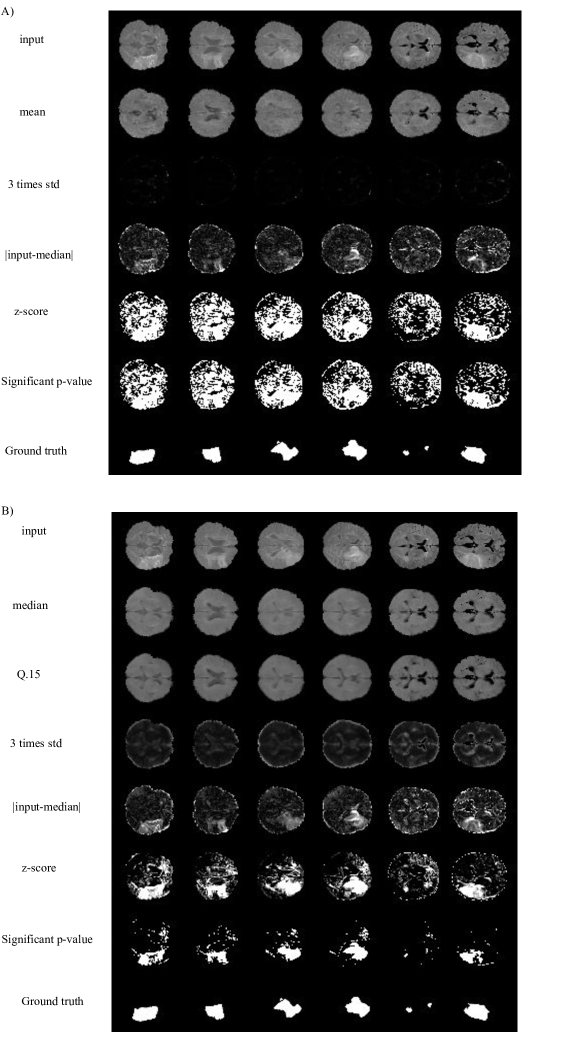

In a second experiment, we trained a VAE with a Gaussian posterior and the QR-VAE as summarized in Figure 4, in both cases estimating conditional mean and variance. Specifically, we estimated the Q0.15subscript𝑄0.15Q_{0.15} and Q0.5subscript𝑄0.5Q_{0.5} quantiles for the QR-VAE and mapped these values to pixel-wise mean and variance. We then used these means and variances to convert image intensities to p-values. Since we are applying the threshold separately at each pixel, there is the potential for a large number of false positives simply because of the number of tests performed. For example, thresholding at an α=0.05𝛼0.05\alpha=0.05 significance level could result in up to 5%percent\% of the pixels being detected as anomalies. In practice the false positive rate is likely to be lower because of spatial correlations between pixels. To avoid an excessive number of false positives we threshold based on corrected p-values calculated to control the False Discovery Rate (FDR), that is the fraction of detected anomalies that are false positives (Benjamini and Hochberg,, 1995). We chose the thresholds corresponding to an FDR corrected p-value of 0.05. As shown in Figure 5, the VAE underestimates the variance, so that most of the brain shows significant p-values, even with FDR correction. On the other hand, the QR-VAE’s thresholded results detect anomalies that reasonably match the ground truth. To produce a quantitative measure of performance, we also computed the area under the ROC curve (AUC) for VAE and QR-VAE. To do this we first computed z-score images by subtracting the mean and normalizing by standard deviation. We then applied a median filtering with a 7×7777\times 7 window. By varying the threshold on the resulting images and comparing it to ground truth, we obtained AUC values of 0.56 for the VAE and 0.94 for the QR-VAE.

Refer to caption

Figure 5: Lesion detection for the ISLES dataset. A) VAE with mean and variance estimation B) QR-VAE. Firs, we normalize each pixel value using the pixel-wise model’s estimates of mean and variance. The resulting z score is then converted to an FDR-corrected p-value and the images are thresholded at a significance level of 0.05. The bottom rows are ground truth based on expert manual segmentation of lesions.